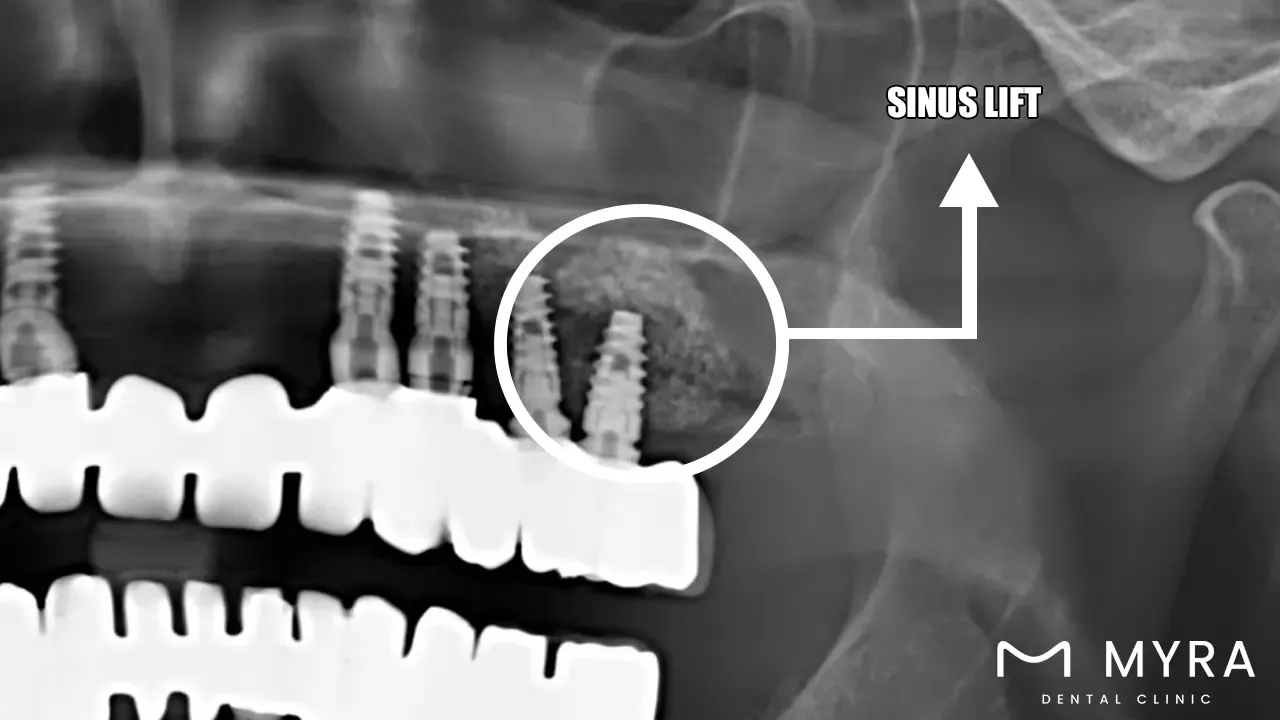

Sinus lift: A sinus lift is a surgical operation that includes grafting bone to the upper jaw in the region of the molars and premolars. It is done in order to alleviate pressure on the sinuses. The objective of the treatment is to boost the quantity of bone that is available for the implantation of dental implants. It is particularly helpful in situations in which the current bone is either too thin or does not have sufficient height because it's so close to the maxillary sinus.

A sinus lift is a surgical technique to increase the quantity of bone in the upper jaw near the molars and premolars so that dental implants are going to be placed. Sinus lifts are necessary for the placement of dental implants because tooth loss causes the maxillary sinus to enlarge, resulting in a loss of bone strength in the jaw.

A small incision is going to need to be made in the gum tissue in order to perform the sinus lift treatment, and a small window is needed to be created in the bone. Bone graft material is inserted between the sinus membrane and the jaw after it has been slightly raised. The wound is stitched up and given time to heal, at which point the graft material and the bone is going to fuse together. Time required for the process ranges from one to two hours, depending on the complexity of the surgery.

A sinus lift is able to improve the quantity of bone that is going to support dental implants, improving the chances of success from 85% to 97%. It is frequently employed in situations when there is insufficient bone elevation in the upper jaw to handle dental implants, especially at the back of the mouth.

Sinus lifts are utilised in the treatment of sinusitis and sinus cysts in addition to its application in the placement of dental implants. However, its primary application is in dentistry, where it is utilised to assist patients obtain both a functional and aesthetically pleasing smile by providing a sturdy base for dental restorations.